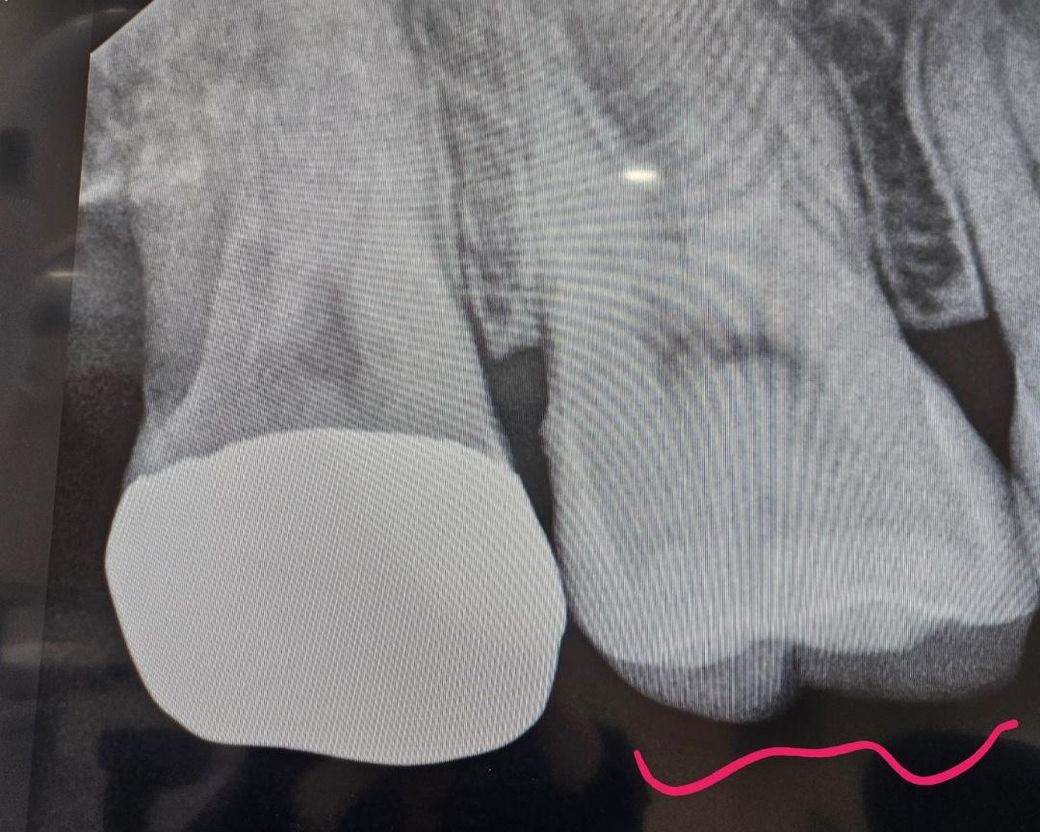

치과사진입니다 봐주세요 어떤지ㅠㅠ

치료받기전 엑스레이입니다.

맨끝치아말고 붉은색 표시한 치아 충치가 많이 깊나요?

<현재는 인레이햇는데 중간부분이 레진떨어졌다고 중간 홈만 레진으로 떼운상태입니다>

신경치료가 답일까요?

신경치료까지 진행해야할 것 같이 보이진 않습니다만 정확한 것은 충치를 제거해봐야 알 수 있습니다.

엑스레이상 신경에 가까울 정도로 깊은 충치는 없는 것으로 보입니다. 다만, 찬물이나 뜨거운물에 지속적으로 시린증상이 있다면 신경치료 가능성도 있긴 합니다. 레진으로 떼운 직후 며칠간은 시린 증상이 있을 수 있습니다.

사진으로만 봤을 경우에는 큰 충치가 보이지 않습니다. 신경치료를 해야 될 가능성은 매우 낮을 것으로 생각됩니다. 정확한 확인을 위해서 치과에서 진료를 받아보는 것을 권유 드립니다

엑스레이 상으로는 충치가 많이 깊어 보이거나 하진 않습니다. 일단 관리하시면서 사용하시면될것같습니다.

상아질 부위까지 다소 손상이 입은 것으로 보이나, 우선 보다 정확한 상태 확인을 위해서는 치과 진료가 필요로 됩니다. 만약 통증이 심한 경우에는 신경치료후 크라운 치료가 필요로 됩니다.